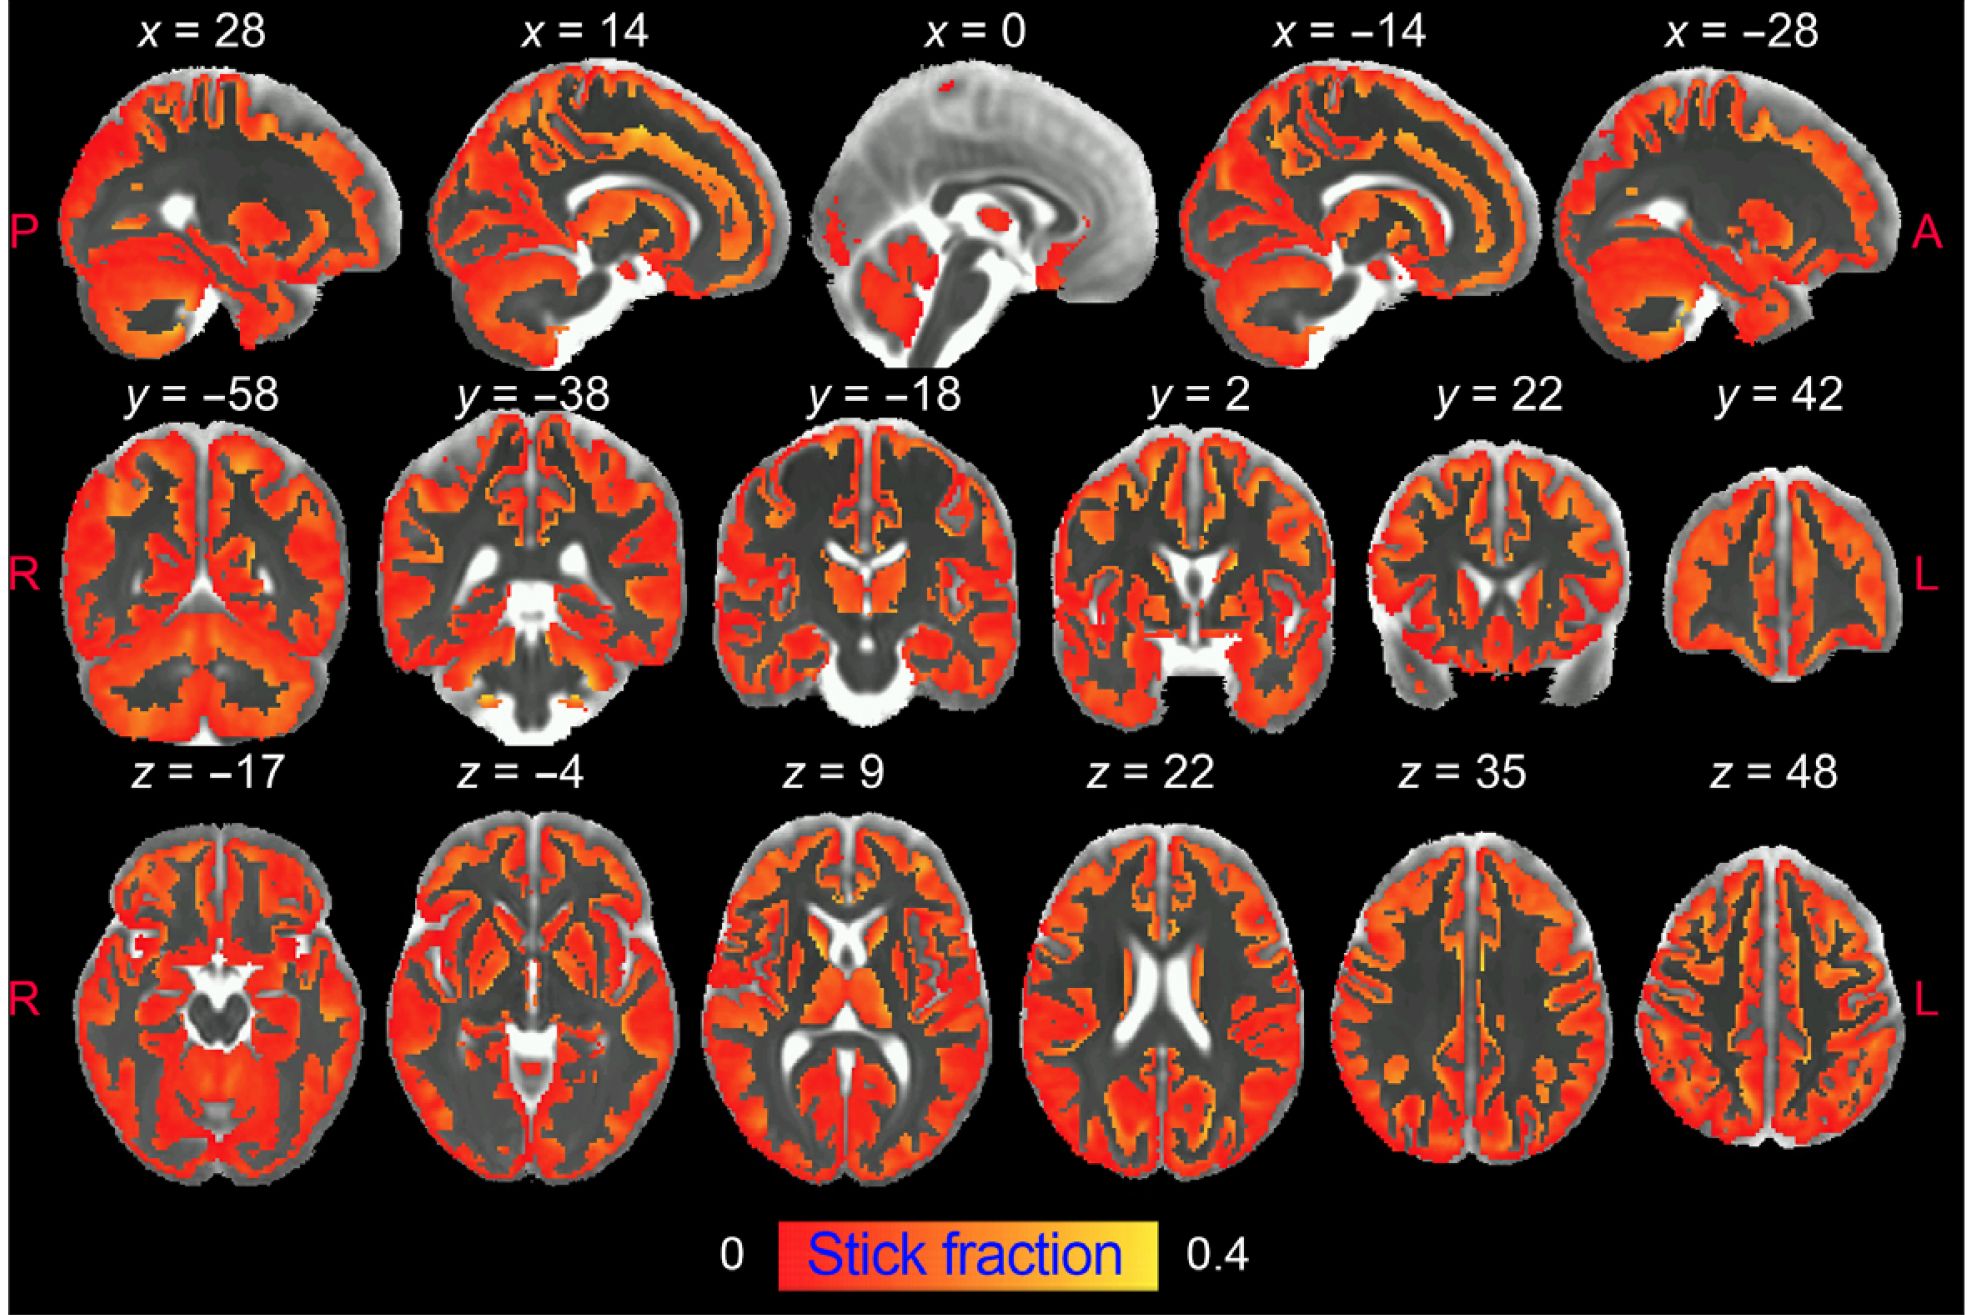

Una investigación ha permitido visualizar por primera vez y con gran detalle la inflamación cerebral utilizando Resonancia Magnética Ponderada por difusión. Esta destallada radiografía de la inflamación no puede obtenerse con una resonancia magnética convencional, sino que requiere secuencias de adquisición de datos y modelos matemáticos especiales.

Frente a estos inconvenientes, la resonancia magnética ponderada por difusión tiene la capacidad única de obtener imágenes de la microestructura cerebral in vivo de forma no invasiva y con alta resolución, al capturar el movimiento aleatorio de las moléculas de agua en el parénquima cerebral para generar contraste en las imágenes de resonancia magnética.

En este estudio, los investigadores del Instituto de Neurociencias (CSIC-UMH) han desarrollado una "estrategia innovadora" que permite obtener imágenes de la activación de la microglía y de los astrocitos en la materia gris del cerebro mediante resonancia magnética ponderada por difusión (dw-MRI).

Este trabajo ha logrado demostrar también el valor traslacional del enfoque utilizado en una cohorte de humanos sanos a alta resolución, "en la que se realiza un análisis de reproducibilidad".

"La asociación significativa con patrones de densidad de microglía conocidos en el cerebro humano apoya la utilidad del método para generar biomarcadores de glía fiables. Creemos que caracterizar, mediante esta técnica, aspectos relevantes de la microestructura tisular durante la inflamación, de forma no invasiva y longitudinal, puede tener un tremendo impacto en nuestra comprensión de la fisiopatología de muchas afecciones cerebrales, y puede transformar la práctica diagnóstica actual y las estrategias de seguimiento del tratamiento de las enfermedades neurodegenerativas", destaca de Santis.